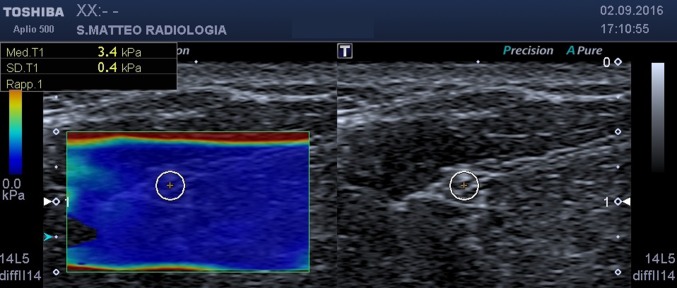

Fig. 1.

SWE, axial scan at mid-forearm. On the left the b-mode image, on the right the elastogram. The circular ROI encloses the median nerve

mid-forearm, between flexor digitorum superficialis and flexor digitorum profundus (Fig. 1);

Using this approach, the values of the stiffness of the nerve at the various sampling points were obtained (Figs. 1, 2, 3). Statistical analysis was performed using MedCalc (MedCalc Software, Ostend, Belgium).